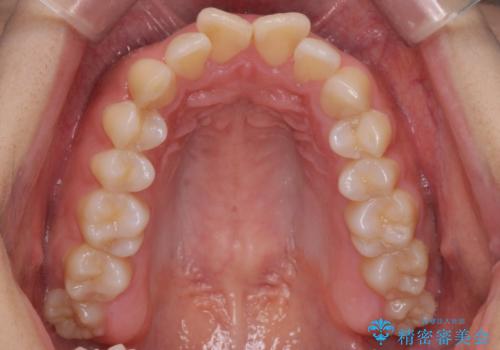

出っ歯の治療 抜かずに 短期間で目立たない治療

- 前歯のがたつきと突出を主訴に来院。

歯を抜かずに非抜歯で治療しました。

治療にも大変満足していただきました。

リファインメントも1回で済んでいます。